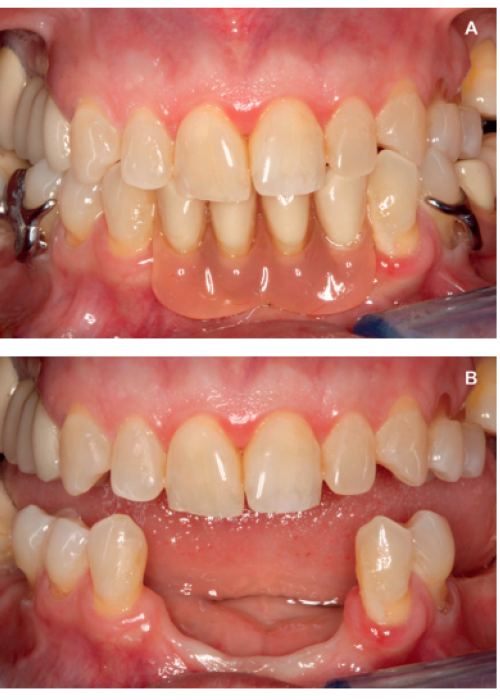

Resolución de un caso con implicación estética en el sector antero-superior. A propósito de un caso